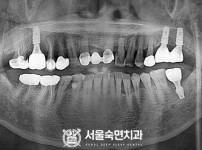

상악동거상술, 뼈이식 / 숙면임플란트 12개 - 오스템임플란트 (김*현님)

해당 게시물은 의료법 제56조에 의거하여 로그인 후 열람이 가능합니다.

구분 임플란트